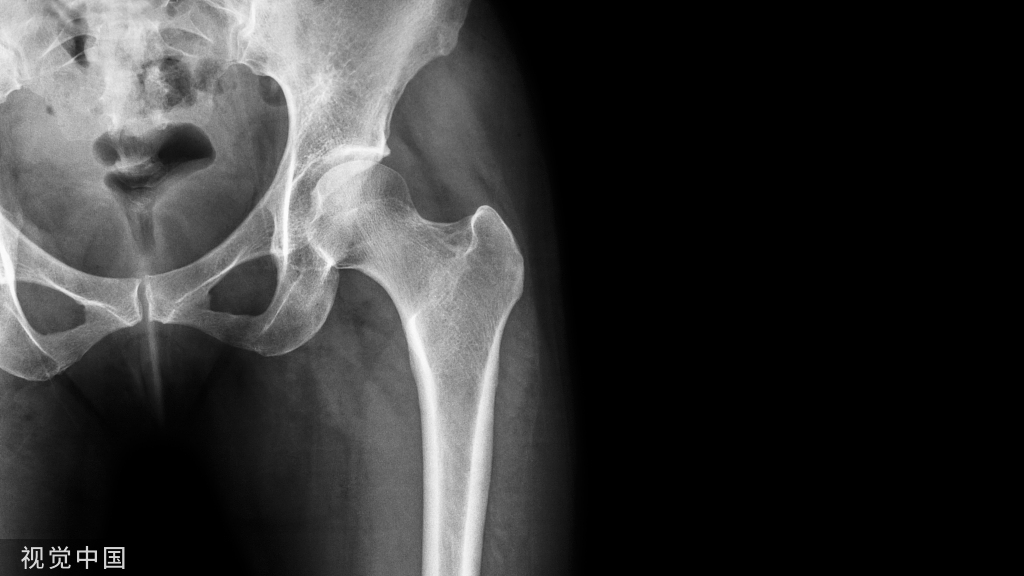

①X线:尺骨阳性变异(尺骨远端伸长)或处于中立位;月骨、三角骨坏死呈低密度小囊状改变以及月骨、三角骨关节面下软骨硬化,病变部位位于月骨尺侧近端和三角骨的腰部;尺骨小头相对关节面下软骨硬化或小囊性变。

其他X线表现包括桡骨远端骨折畸形愈合,桡骨远端异常背倾畸形和桡骨近端骨折畸形愈合导致桡骨缩短,尺桡远侧关节脱位。因为尺骨头与月骨解剖位置邻近,易发生撞击且易形成桥连状态(尺骨头与月骨连接)而产生持久性压迫,因此在尺骨阳性变异的患者中月骨发病率明显大于三角骨。

X线测量:在标准后前位X线平片测量尺骨变异,采用Gelberman等的平行线法(尺骨头关节面的平行线与乙状切迹最远端关节面的平行线之间的位置距离差)。

- 尺骨头长于桡骨为阳性变异;

- 尺骨头短于桡骨为阴性变异;

- 两者相等为中性变异。

对症状较重者、常规X线后前位显示尺骨变异呈阴性或中性者,采用握拳、腕旋前位摄片。